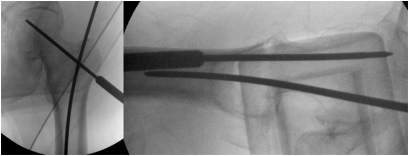

对于钩杆撬拨技术,将骨钩通过切口沿股骨近端前侧皮质插入,并将尖端导入近端和远端骨块之间的骨折部位(图3)。

图 3. 在骨模型(左图)和X光片(右图)中展示的将骨钩插入骨折部位。

在轴位侧位片和前后位片上获得满意的复位后,如果需要,我们在前方插入一枚2.0毫米斯氏针用于复位的临时固定(图5)。

图 5. 前方用克氏针临时固定以避免干扰股骨近端防旋髓内钉螺旋刀片,显示在临时固定后术中透视前后位(左)和侧位(右)视图中内侧和前侧皮质无移位。

这枚斯氏针最好放置于股骨颈前三分之一处,以避免干扰股骨近端防旋髓内钉(PFNA)的螺旋刀片。